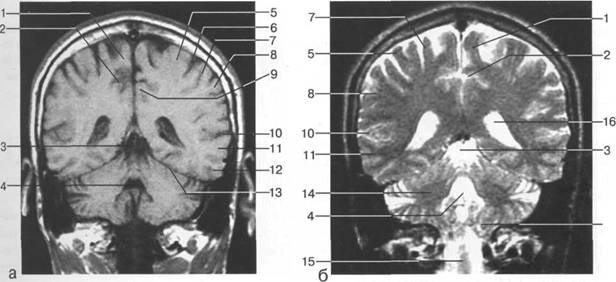

В латеральных отделах дно передней череп 13513u2010n 85;ой ямки образовано крышами глазниц, а в центральном - продырявленной пластинкой. Базальные отделы лобных долей представлены ко

ные извилины (рис. 1.10). Структуры средней череп 13513u2010n 85;ой ямки ограничены спереди малым крылом основной кости, снизу - большим крылом, сзади - передней поверхностью пирами «edge» «bone»

Содержимое средней череп 13513u2010n 85;ой ямки представлено базальными отделами височной доли.

ристый синус с внутренней сонной артерией, череп 13513u2010n 85;о-мозговые нервы) дифференцировать тральные отделы основания череп 13513u2010n 72; занимает турецкое седло. В полости турецкого седла ви